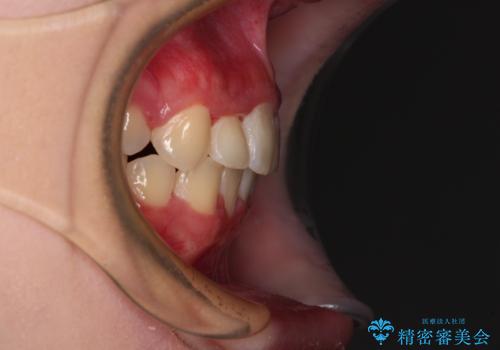

インビザラインが続けられない ワイヤー矯正での抜歯矯正 その2

- 八重歯やデコボコをインビザラインで治療したいとのことで来院された患者様です。

インビザライン単体で治療を行うには叢生が強いと判断されたため、事前にワイヤー装置で抜歯矯正を行い、ある程度改善してからインビザラインにて仕上げていくこととしました。